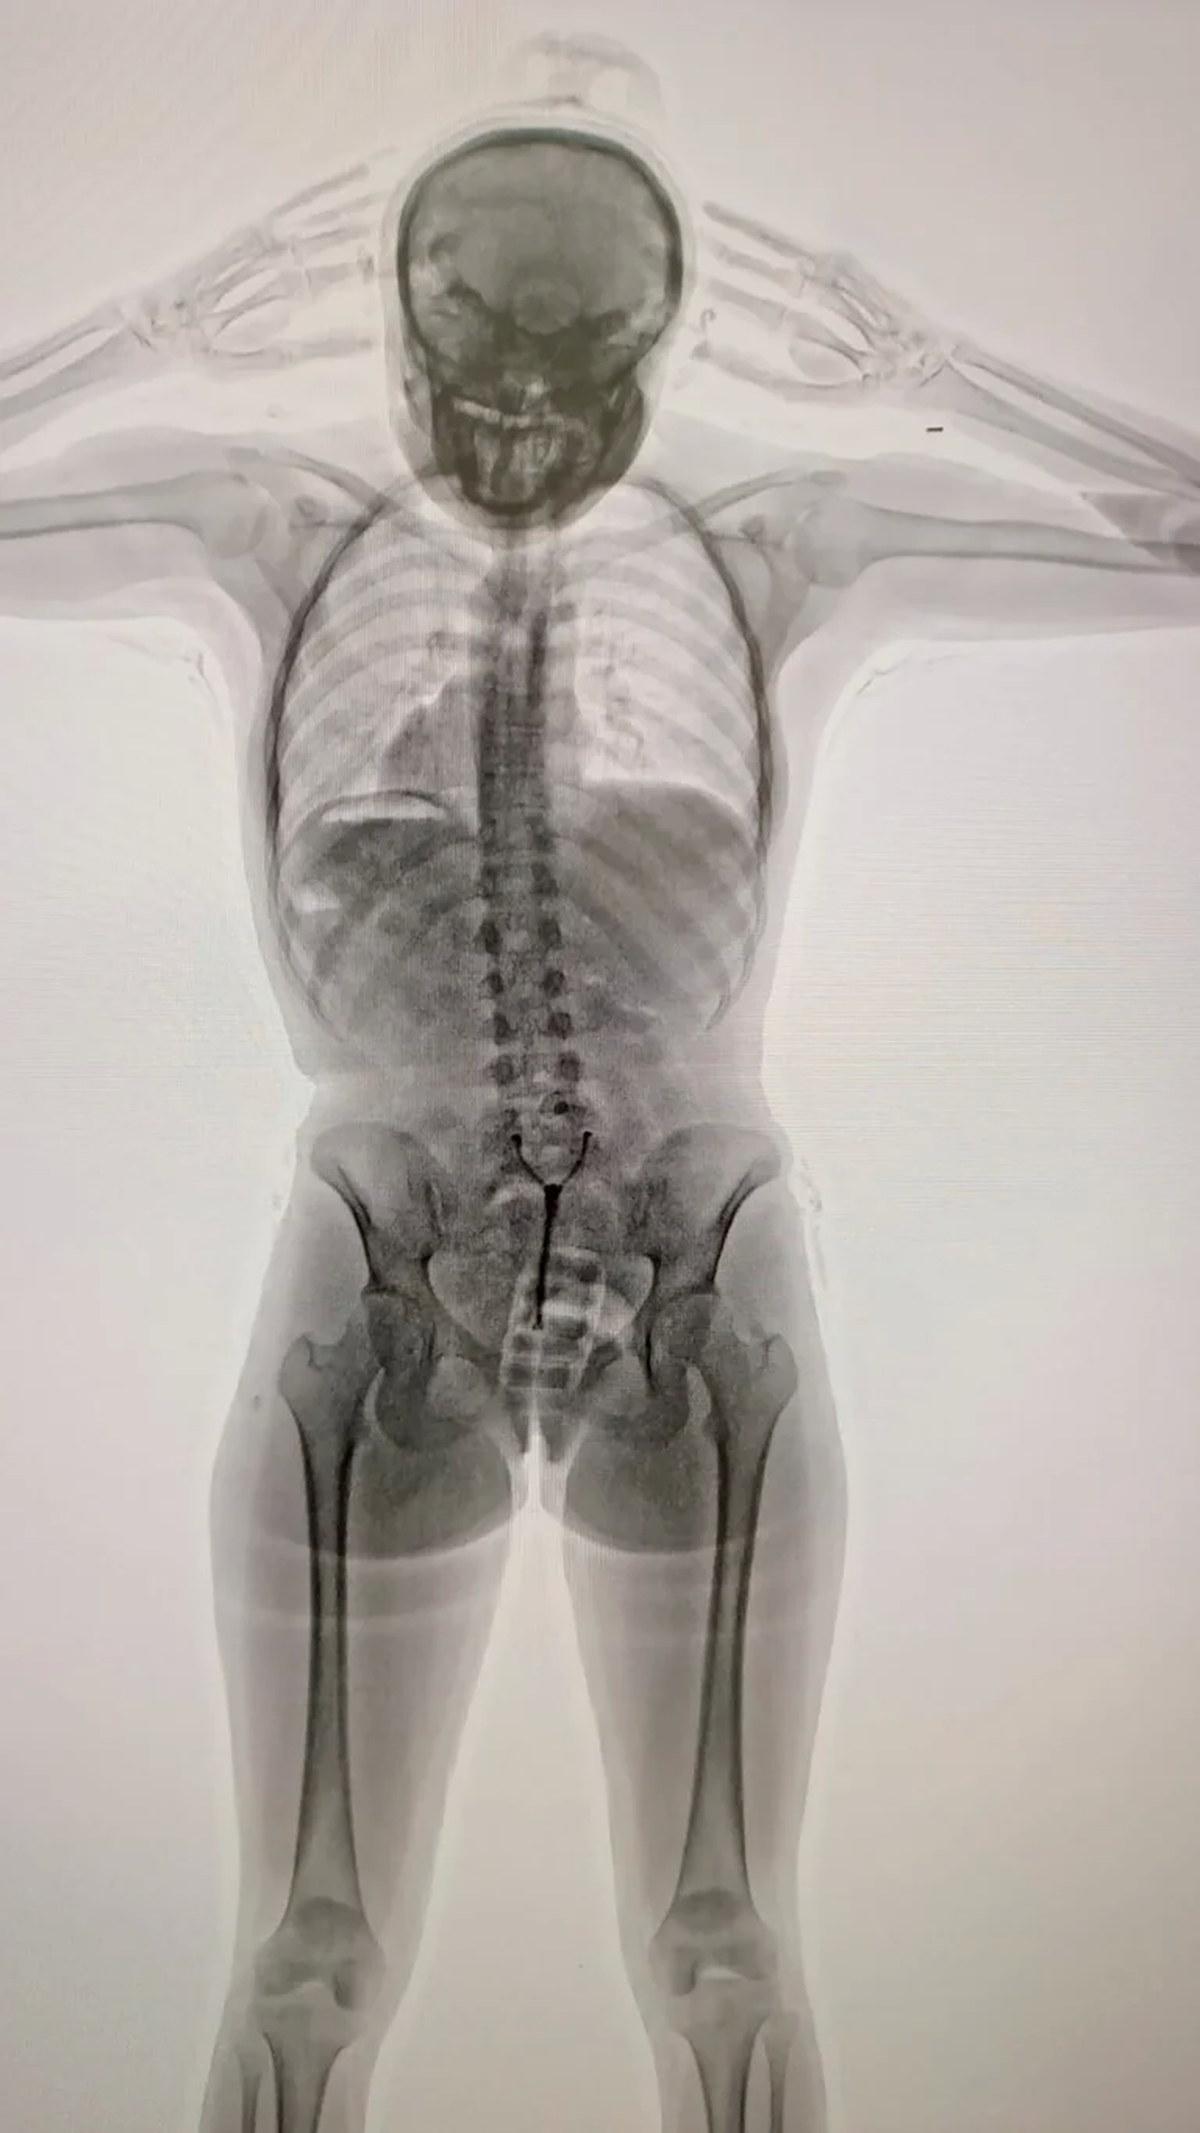

La persona en cuestión era una joven de 20 años que llevaba los estupefacientes dentro de su organismo. La descubrieron mediante un control de Rayos X.

Las autoridades notaron un extraño comportamiento de la joven, pero la principal causa por los cuales los Inspectores de Aduana seleccionaron al a joven para una entrevista previa al vuelo fue su nerviosismo, incongruencia y dubitante. Ante la situación, efectivos de la Policía de Seguridad Aeroportuaria (PSA) se hicieron presentes en el lugar y en conjunto con funcionarios de la Dirección General de Aduanas y personal AIRCOP, procedieron a realizarle un control corporal no invasivo mediante el equipo de Rayos X delante de la presencia de testigos.

En ese entonces fue que notaron la extrañes de la situación: identificaron la posible presencia de elementos extraños dentro del organismo de la joven de 20 años, principalmente en su zona genital. En consecuencia, las autoridades obtuvieron la orden judicial para el procedimiento de requisa, pero fue ahí que la "mula" confesó y manifestó que transportaba estupefacientes dentro de su vagina. En otras palabras, había introducido en su cuerpo un profiláctico con 11 cápsulas de cocaína, de aproximadamente 10 gramos cada una.

Pero eso no fue todo. La joven fue trasladada al Hospital de Ezeiza bajo la custodia de la PSA. Allí, evacuó las cápsulas detectadas en las imágenes del escáner, pero finalmente eran más de lo que ella había confesado: otras 67 cápsulas estaban dentro de su sistema digestivo. Dicho esto, en total llevaba en su cuerpo 742 gramos de estupefacientes.